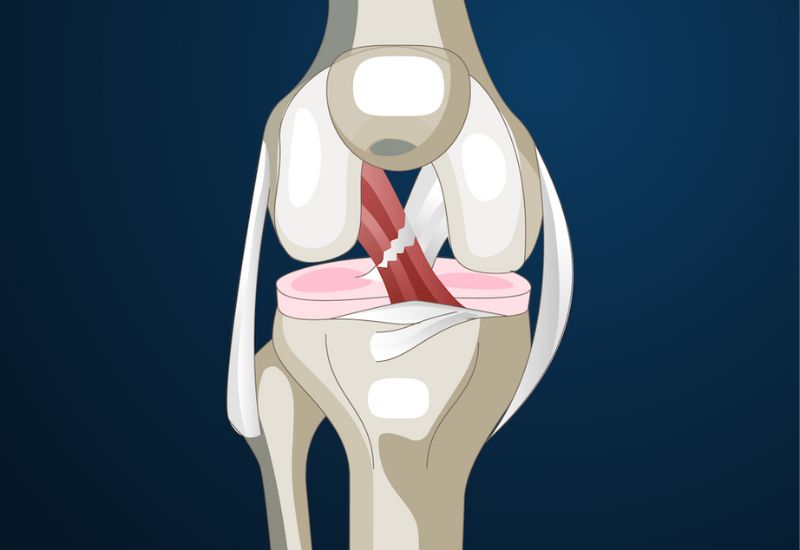

Khớp gối là một khớp phức tạp, có sự tham gia của nhiều dây chằng để đảm bảo tính ổn định trong quá trình vận động. Trong đó, dây chằng chéo trước (ACL – anterior cruciate ligament) là một trong những dây chằng quan trọng nhất, giữ vai trò kiểm soát chuyển động trượt ra trước của xương chày so với xương đùi và giúp khớp gối vững vàng khi xoay hoặc đổi hướng đột ngột.

Dây chằng chéo trước nằm sâu trong khớp, bắt chéo với dây chằng chéo sau, tạo thành hệ thống giữ ổn định ở trung tâm khớp gối. Khi dây chằng này bị đứt, khớp gối dễ mất ổn định, dễ trật bánh chè và tổn thương sụn chêm, từ đó ảnh hưởng nghiêm trọng đến khả năng vận động, đặc biệt là ở những người có lối sống năng động hoặc cần vận động chuyên nghiệp.

Hình ảnh minh họa đứt dây chằng chéo trước